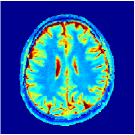

According to [44] as we progress into deeper layers, partitions will be subdivided into smaller segments in a hierarchal fashion. This can be observed in Figure 2 where we adopted the above routine for the T1/T2 encoding MRF sequence used in our experiments and visualised multi-scale (from coarse-to-fine) partitions obtained after each residual layer. The Bloch response manifold is sampled across fine-gridded T1/T2 values (i.e. MRF dictionary) to visualise the intersection of the input space segments with this manifold (results are visualised across the three dominant principal component axes). MRFResnet encoder learns about a thousand partitions for its end-to-end mapping . In the light of (16) we know that for each partition the network implicitly encodes deep matched-filters (the rows of or alternatively ) and an offset term to locally linearly regress the T1/T2 outputs in that segment. As such instead of memorising 100K dictionary atoms used for training, the network learns a compact piece-wise affine approximation to the Bloch manifold projection (5) as a rapid and memory-efficient alternative to DM’s point-wise approximation (7). The total number of parameters used by the MRFResnet (Table I) are two hundreds times less than the size of the dimension-reduced MRF dictionary. Figure 3 shows the Bloch responses for a range of T1/T2 values, as well as deep matched-filters learned by MRFResnet to predict each of these quantities in this range from noisy inputs. Computed through (17), match-filters are one-dimensional analogues of the saliency maps a.k.a. deep dream images [49], measuring sensitivities of the T1/T2 output neurons with respect to the inputs.